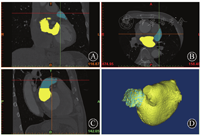

MIMICS(Materialise's interactive medical image control system)是比利时Materialise公司设计的交互式医学影像控制系统,可利用CT数据集的横断面、矢状面、冠状面3个正交平面重建局部解剖三维结构,准确测量目标区域的几何参数[22,23]。将患者冠脉CTA影像导入MIMICS 17.0软件中,选择心动周期中心室收缩期(此时心房处于最大容积)相位窗图像作为三维重建原始数据。先后利用软件中的阈值切割、区域增长、模块编辑、三维计算、三维编辑等功能,重建患者左心房、左心耳及肺静脉三维模型(图1),并对相关数据进行测量(图2)。患者冠脉CTA中左心房、左心耳的所有数值均在非同日重复测量2~3次,取所有测量值的平均值。

A、B、C分别为冠脉CTA冠状面、横断面、矢状面3个正交平面,D为利用上述3个正交平面重建的左心房及左心耳三维结构